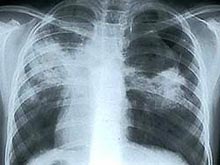

Международные исследователи утверждают, что сделали "важный шаг" в исследовании туберкулеза. При помощи ДНК они научились определять носителей инфекции, у которых болезнь разовьется в активную форму. Как передает BBC, такой тест позволит выявить недуг на ранней стадии и, возможно, спасет многие жизни.

Туберкулез - это инфекционное вирусное заболевание легких, вызывающее такие симптомы, как кашель, боли в груди и потерю веса. Заражение туберкулезом в мире происходит каждую секунду. Однако в активную форму болезнь переходит лишь у каждого десятого инфицированного.

До сих пор медики могли определить человека, зараженного туберкулезом, но не могли предсказать, у кого именно болезнь будет развиваться. Ученые из Великобритании, США и Южной Африки исследовали анализы крови больных с активным туберкулезом. Примерно у 10% пациентов с латентной формой инфекции они обнаружили одинаковые генетические маркеры, которые означали, что эти люди являются кандидатами на полномасштабную форму туберкулеза.

По словам ученых, в последние годы в диагностике латентной туберкулезной инфекции был достигнут значительный прогресс. Однако зачастую диагноз бывает трудно сделать, пока болезнь не станет заразной для окружающих. Это особенно опасно в развивающихся странах, которые обладают меньшими ресурсами для предупреждения и лечения туберкулеза.

"Если мы сможем предсказывать, у кого из так называемых носителей туберкулеза болезнь продолжит прогрессировать в полномасштабную форму, это будет иметь серьезные последствия для предотвращения глобальной эпидемии", - считает ведущий исследователь Национального института медицинских исследщований в Лондоне, доктор Анна О'Гарра.